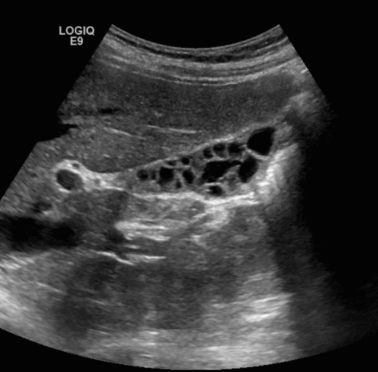

3) Multiseptate GB

다발성의 얇은 격벽 구조에 의해 크기가 서로 다른 여러 부분으로 나누어져 있다. 무증상이며 기능적으로도 아무 문제없다.